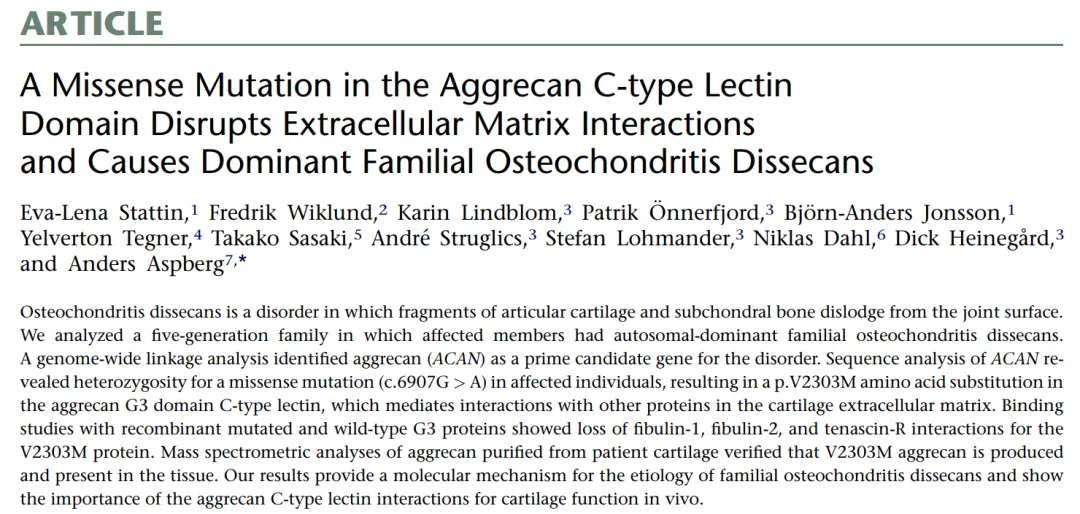

侏儒症是一种由基因疾病引起的,会导致短小身材和骨骼不成比例生长的疾病。在侏儒症相关疾病机制研究中, 于默尔大学医院研究团队在The American Journal of Human Genetics杂志上,发表了一篇题为“A Missense Mutation in the Aggrecan C-type Lectin Domain Disrupts Extracellular Matrix Interactions and Causes Dominant Familial Osteochondritis Dissecans”的文章。该团队分析了一个患病的五代家庭成员,确定软骨主要成分Aggrecan蛋白的基因 ACAN为该疾病的主要位点,并且发现由于Aggrecan蛋白的C型凝集素结构域的错义突变导致了其与细胞外基质的相互作用能力丧失,进而造成了常染色体显性遗传的剥脱性骨软骨炎。在整个疾病相关机制的研究中,Biacore对其突变与患病原因的相关性提供了关键证据。

图2 文章截图

剥脱性骨软骨炎是软骨和软骨下骨与周围组织分离,主要影响膝关节、踝关节和肘关节,涉及骨骼发育紊乱,不成比例的生长和骨骼变形(图3)。研究人员对一个五代遗传性剥脱性骨软骨炎家族进行了全基因组连锁分析后,发现Aggrecan蛋白G3结构域发生了一个错义突变p.V2303M。将相关G3结构域变体与多种细胞外基质蛋白重组表达后,使用Biacore进行相互作用分析。